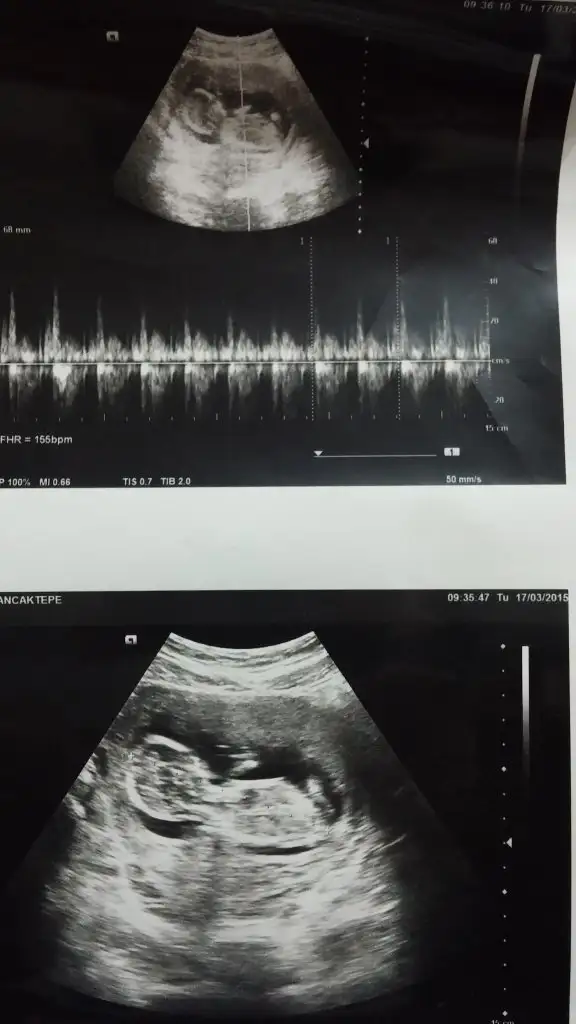

Bir süredir hastaydım. İşler de çok yoğun iş yerinde pek giremiyorum. Biraz kahverengi lekelenmem olmuştu. Normalde 16. haftada gidecektim ama, doktor gel bakalım dedi. Dün gittim. 14+6 çıktı. Doktor %90 erkek dedi :) Bana da gösterdi. Baya baya erkek yani aslında :KK48: ama kordonla falan karışabiliyor bazen dedi. 16'da karışmayacak duruma gelir:KK48: net söyleriz dedi. Yalnız tam gördüğü anı fotoğraflamadı. Diğer fotosu da net değil. Sırtı görünüyordu zaten, çekmedim fotosunu. Eski yüklediklerimi bir daha yükliyim kızlar. O zaman kız diyen de vardı erkek de. 2. fotoya genelde kız demiştiniz galiba. Bakın bakalım :))

• Bebişim 13+2.webp

Bebişim 13+2.webp

32,4 KB · Görüntüleme: 167